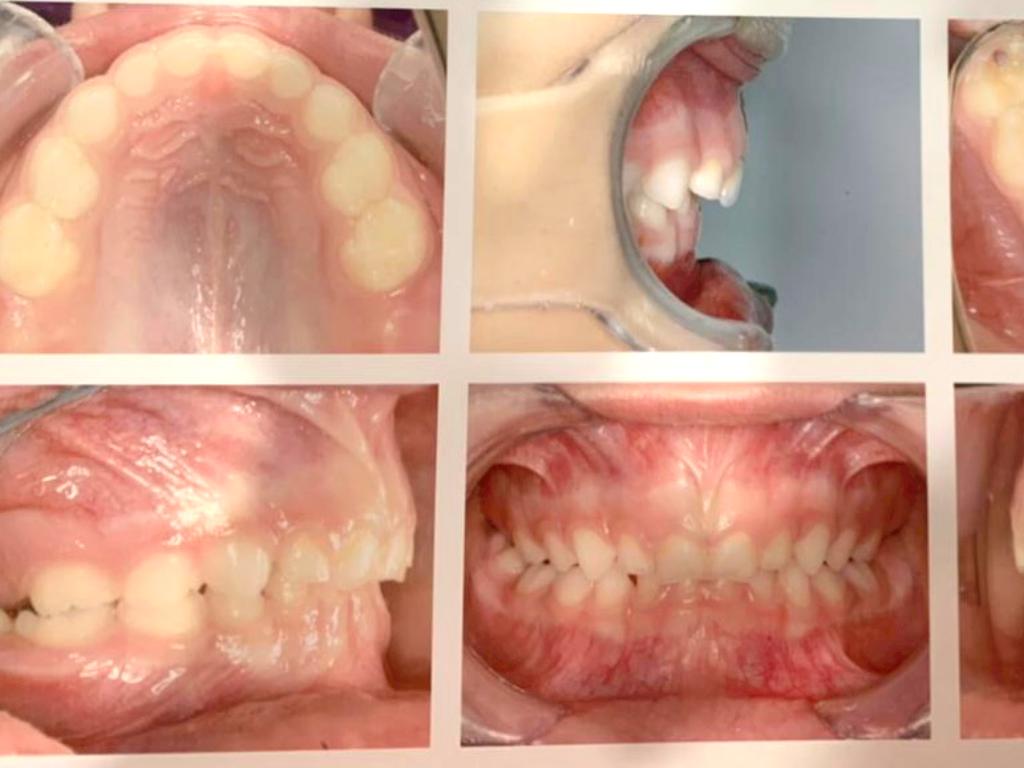

DENTAL

Mordida profunda

Falta de espacio para dientes permanentes